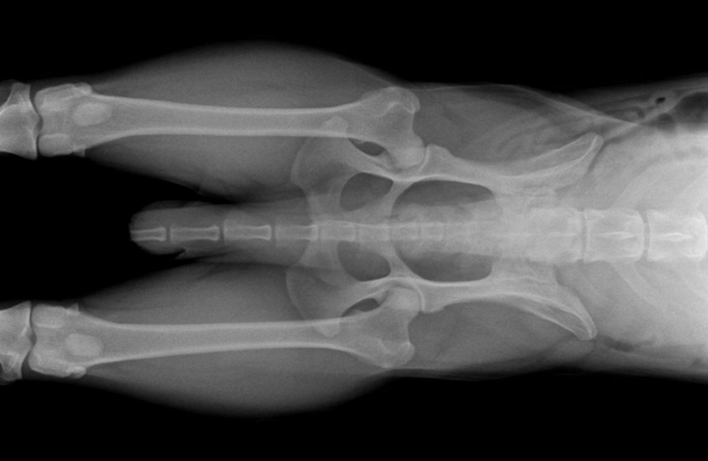

RTG Dysplazie loketního kloubu (DLK)